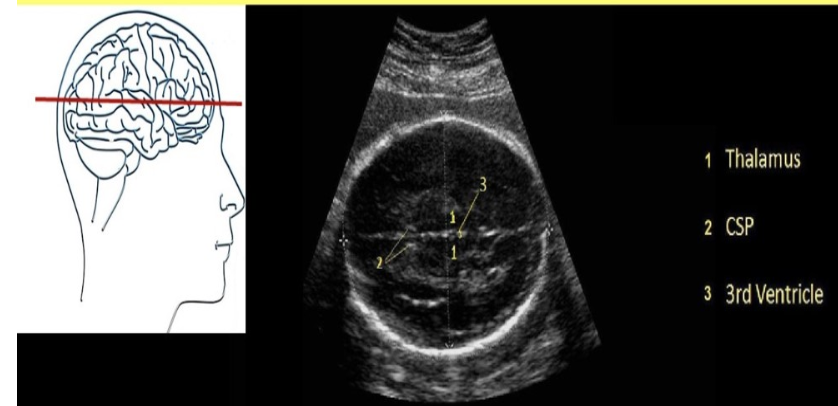

the correct cranial level for BPD + HC assessment is

.

a) Transverse axial view of the fetal skull at the level of the cavum septum pellucidum, third ventricle, and thalamus

b) Transverse axial view of the fetal skull at the level of the cerebellum and cisterna magna

c) Coronal view of the fetal skull at the level of the cavum septum pellucidum, third ventricle and thalamus

d) Transverse axial view of the fetal skull at the level of the lateral ventricles and choroid plexus